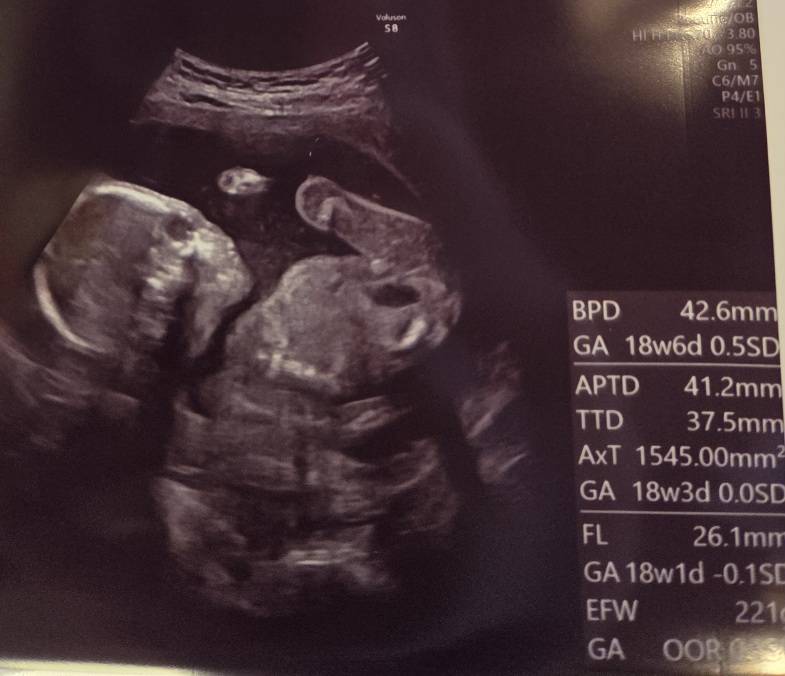

妊娠5ヶ月目、3回目の

妊婦検診がありました。

タイミングよく赤ちゃん起きてくれてて

もぞもぞ動いてくれてたのを見れました!!

あくびもしてて大きな口あけてたよ😌

気になる性別は……

「確定じゃないけど、ついてるっぽいかも」

と言うことで、男の子かも!?

今日の赤ちゃんの向きでは

うまくエコーで見えなかったらしいです。

男の子のように見えていても

へその緒と見間違えることもあるらしくて

今回はそのあたりが微妙な感じ?

先生からは、特に異常はないですね、って